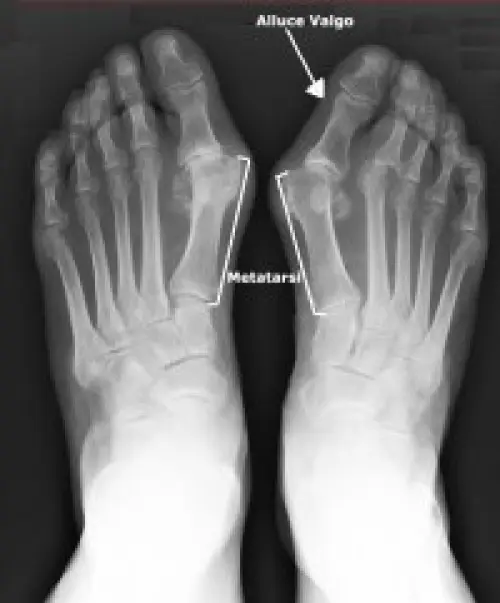

Questo tipo di intervento chirurgico è ideale per le forme lievi e moderate di alluce valgo, quando la deviazione non supera precisi valori angolari (non più di 20° tra gli assi del primo e secondo metatarso, cioè le ossa che precedono le dita). Questo significa che la chirurgia soft va bene quando è ancora possibile riallineare manualmente l 'alluce. Comunque, prima di ricorrervi, è necessario fare una radiografia del piede, effettuata in posizione eretta: solo così è possibile valutare bene quali sono le alterazioni strutturali che lo scheletro del piede ha subito a causa della deformità dell' alluce, e sapere con certezza se la via percutanea è quella giusta. E, in tal caso, si possono operare entrambi i piedi con un unico intervento.